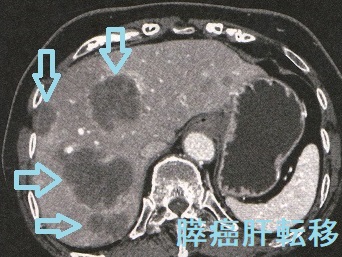

甲状腺乳頭癌の膵臓転移 造影CT(日本消化器外科学会雑誌.2011;44(4):442-448)

甲状腺乳頭癌に対し甲状腺全摘10年後、頸部リンパ節再発を認め、同時にFDG-PET/CTで集積し、造影CTで造影効果のある膵頭部腫瘍を発見。不思議にも他臓器転移なく、膵内分泌腫瘍の可能性も考えられたが、膵頭十二指腸切除術後の病理組織学的検査で甲状腺乳頭癌の膵転移が確定(日本消化器外科学会雑誌.2011;44(4):442-448)。